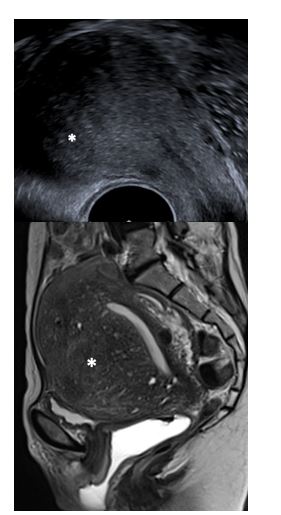

Fig 2 Endométriome Echo

• Echographie endovaginale , coupe axiale passant par l’ovaire gauche

• Echographie endovaginale , acquisition 3D et reconstructions multi planaires passant par l’ovaire gauche

• Echographie endovaginale , coupe axiale passant par les ovaires, adhérents à la face postérieure de l’utérus réalisant un aspect de « kissing-ovaries »

Endométriome(*), kyste uniloculé hypoéchogène homogène

Fig 5 Endométriome IRM

• IRM coupe sagittale T2 passant par l’utérus

• IRM coupe axiale T1FS passant par l’ovaire gauche

Endométriome gauche (*), kyste uniloculé en hypo signal T2 avec shading, et hyper signal T1